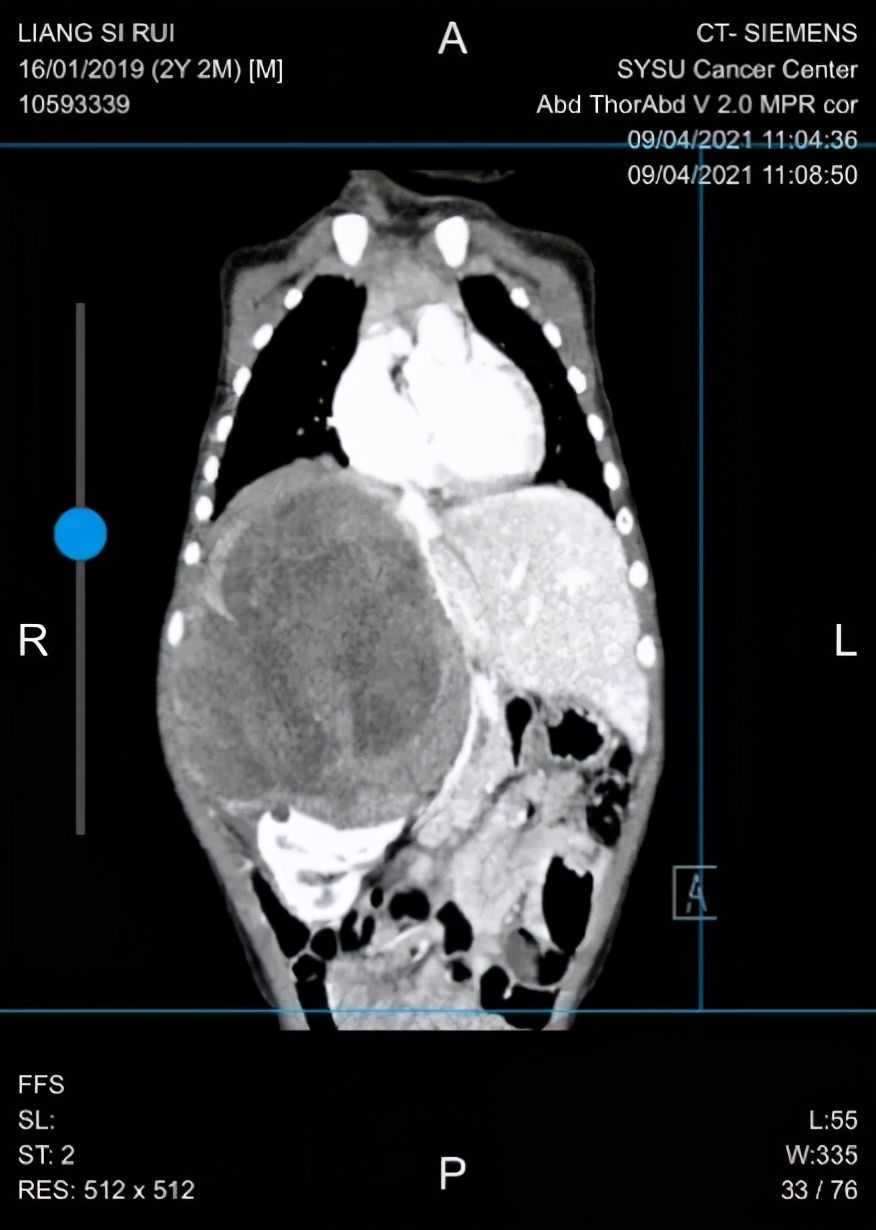

影像显示

经过新辅助化疗,复查CT等影像学检查提示肿瘤直径约为9厘米,较前缩小,手术切除可能性较前提高。泌尿外科刘卓炜教授、肝胆外科韦玮主任医师和手术麻醉科多学科会诊讨论,最后决定采用根治性手术的最佳方案,专家团队与患者及家属充分沟通,得到了他们的理解和支持。

5月17日,泌尿外科刘卓炜教授主刀,肝脏外科韦玮主任医师和泌尿外科李向东医生担任助手,共同为小睿进行手术。如同术前评估,术中见右肾大小约10*10cm的肿瘤且肿瘤内侧部分与下腔静脉粘连紧密。刘卓炜副院长和韦玮主任医师首先仔细松解肝肾韧带,钝性结合锐性分离肝肾间粘连,将肝脏推向左侧避免损伤。完整暴露肿瘤后,逐渐发现肿瘤与下腔静脉粘连过于紧密,分离肿瘤的过程不得已使下腔静脉产生了0.5cm裂口,刘卓炜教授沉着冷静,快速应对,仔细修补血管,避免了大出血。